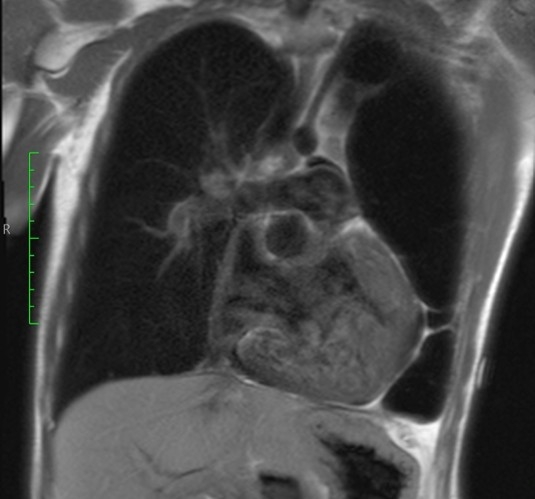

We describe a case of a male patient with left-sided CDH diagnosed prenatally and surgically repaired in the neonatal period. He developed severe PH requiring extracorporeal membrane oxygenation (ECMO), prostaglandins, and prolonged dual therapy with endothelin receptor antagonists (bosentan, macitentan). He was weaned off oxygen at age 3 but required re-initiation at 17 due to progressive desaturation. Additional congenital anomalies included repaired aortic coarctation and multiple abdominal surgeries. At age 20, clinical deterioration followed the introduction of selexipag, with worsening hypoxemia, increased oxygen requirements, and suspicion of pulmonary vascular disease progression. Cardiac catheterization and cross-sectional imaging were attempted but were limited by profound hypoxemia and instability.

Descriptive findings revealed resting oxygen saturations of 82–85% on 4 L/min supplemental oxygen, WHO functional class III, and echocardiographic signs of right ventricular overload. Laboratory markers showed elevated NT-proBNP (1,347 pg/mL). No evidence of acute thromboembolism was found. Clinical worsening was temporally associated with selexipag initiation. Drug withdrawal led to partial functional and oxygenation recovery. Based on clinical trajectory and ancillary testing, Group 3 PH secondary to developmental lung disease was the working diagnosis. The case was discussed at a national PH board, confirming the suspicion of irreversible pulmonary vascular compromise.